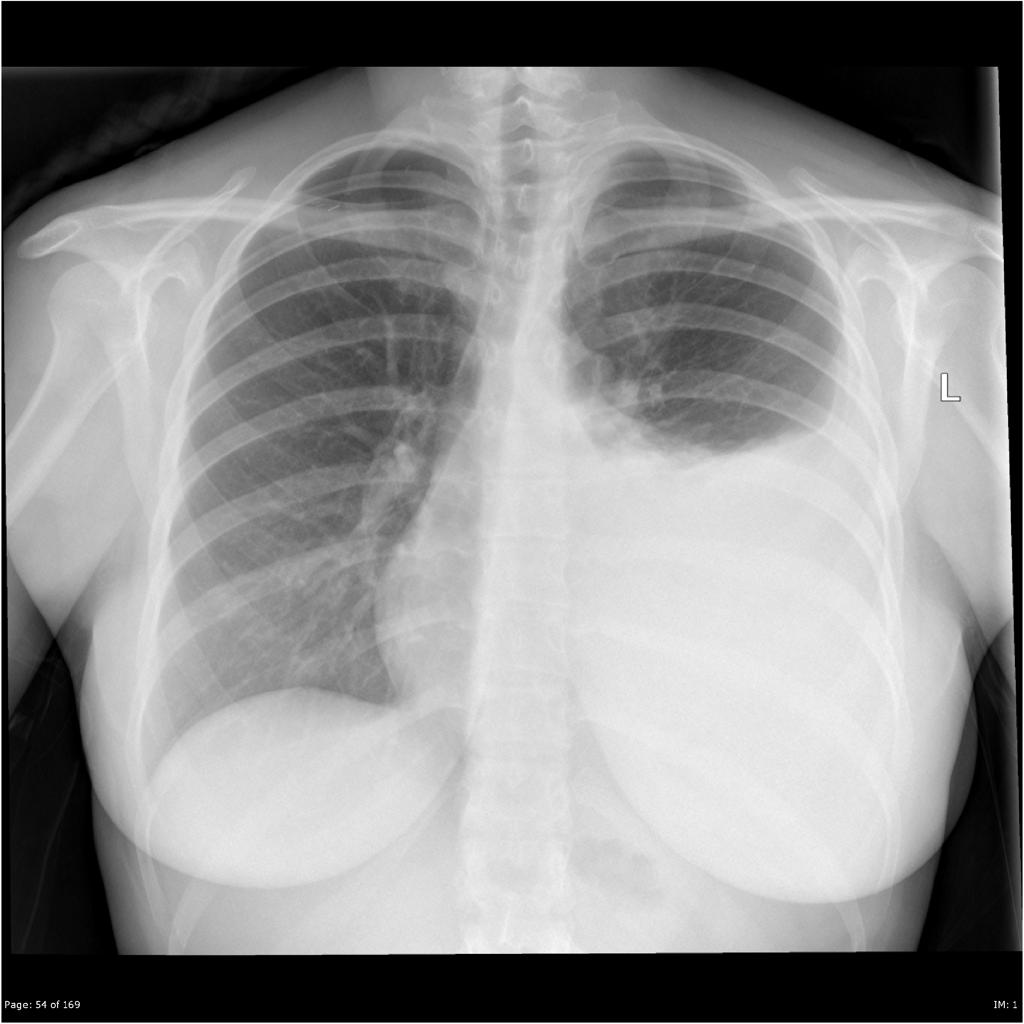

Cureus Acute Myeloid Leukemia Complicated by Hyperleukocytosis and Chest X-Ray To Diagnose Leukemia If the scan finds an abnormal. Although the thorax is uncommonly involved, it may occur in the lungs, pleura, mediastinum, chest. a ct scan of the chest or abdomen can help detect an enlarged lymph node or cancers in the liver, pancreas, lungs, bones and. — myeloid sarcoma. — physical exams for diagnosing leukemia. Consider seeking medical. Chest X-Ray To Diagnose Leukemia.

From www.cureus.com